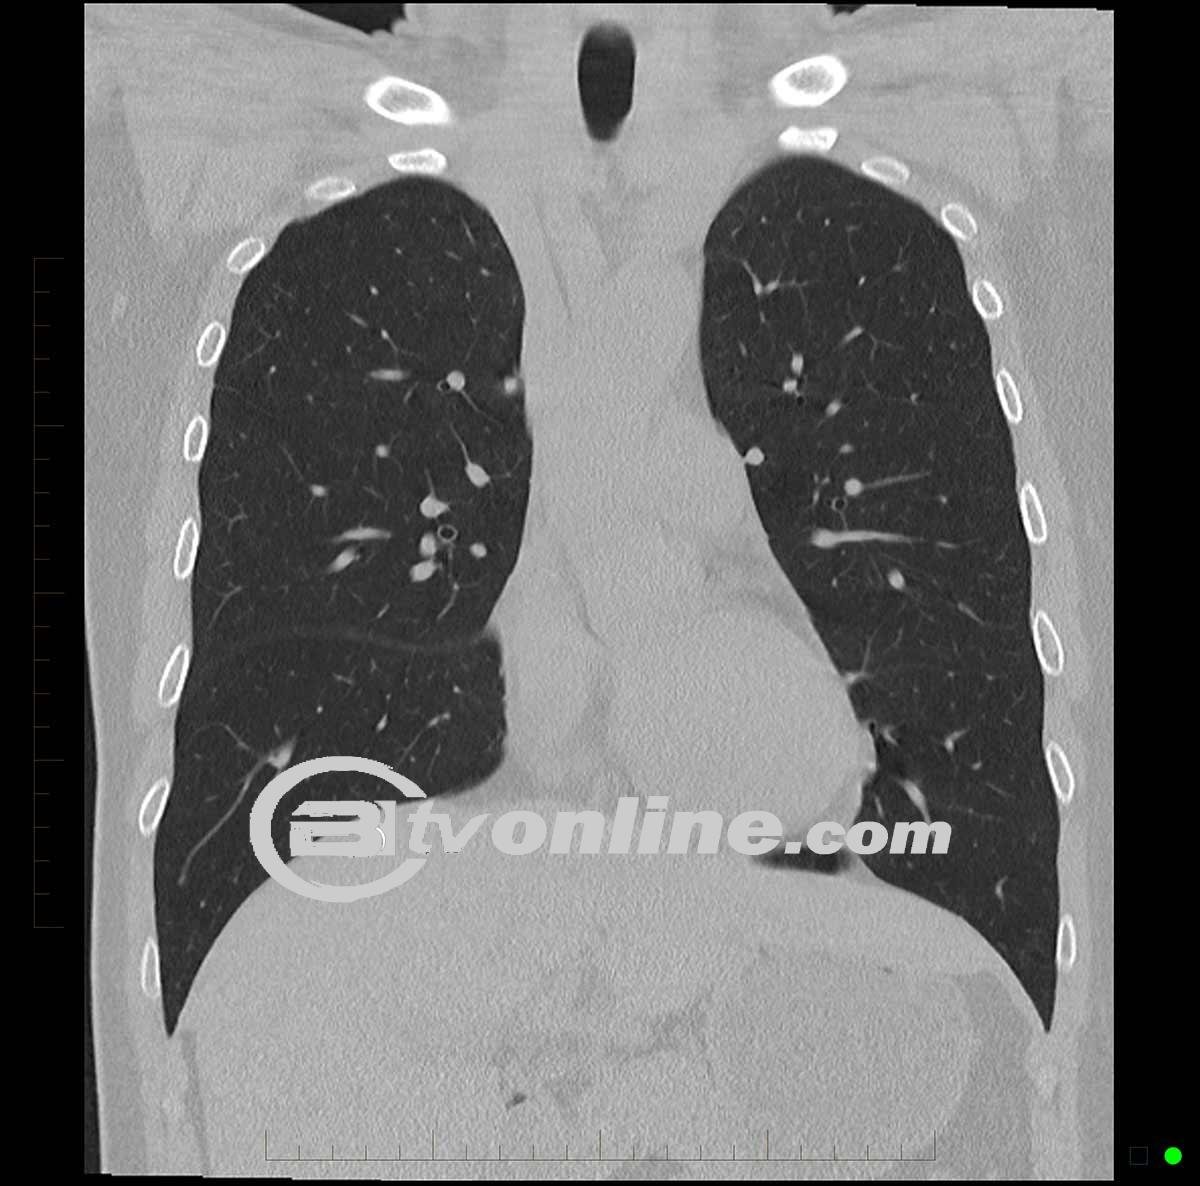

BITVONLINE.COM – Kanker paru-paru merupakan salah satu jenis kanker yang paling umum dan mematikan, sering kali ditandai dengan keluhan pada sistem pernapasan. Batuk adalah salah satu gejala yang paling sering dialami pasien, namun seringkali sulit dibedakan dari penyakit pernapasan lainnya. Spesialis paru-paru dr. Agus Dwi Susanto, SpP, mengungkapkan bahwa batuk yang diduga sebagai gejala kanker paru-paru biasanya disertai dengan kondisi lain yang lebih mengkhawatirkan.

Deteksi dini dapat dilakukan melalui foto rontgen atau CT scan thorax, yang dapat memberikan gambaran rinci dari paru-paru dan jaringan di sekitarnya. Hal ini sangat penting, karena diagnosis yang cepat dapat meningkatkan peluang pengobatan yang sukses.